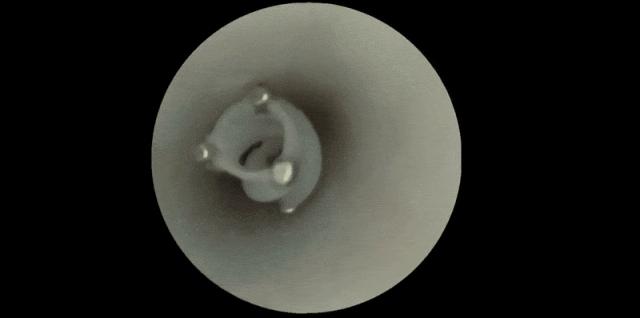

這一次,團隊保留了其中最關鍵的結構——螺旋狀的側翼、中空的管道和開槽的外壁,並將原本指甲蓋大小的裝置縮小到了直徑與長度僅幾毫米,恰好適合在直徑3~5毫米的大腦血管中穿行。

機器人進入血管後,外部施加的旋轉磁場會驅動它快速旋轉。特殊的中空設計使得它在前進時會產生負壓,液體從前端吸入,再從後端和側槽噴出,從而推動機器人前行。

機器人的特殊結構,使其能在血管中快速前進 | 參考文獻[2]